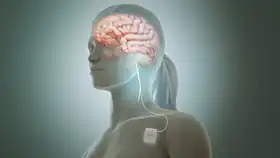

Neurostimulation may also improve seizure control.[6] The vagus nerve stimulator (VNS) is surgically implanted in the chest, and delivers programmed electrical stimulation to the vagus nerve in the neck.[38] The responsive neurostimulation device is implanted in the skull, monitors electrical brain activity for seizures, and responds to seizures with programmed electrical stimulation to one or two brain areas.[39] Programmed deep brain stimulation of the anterior thalamic nucleus may treat seizures arising from more than 2 brain areas.[6]